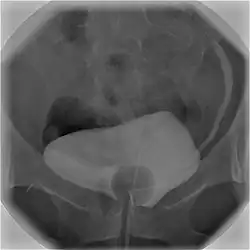

Cystographie

La cystographie est une radiographie qui permet d'explorer les parois de la vessie et de l'urètre. Cet examen utilise des rayons X et un produit à base d'iode. Ce dernier est le plus souvent injecté directement dans la vessie à l'aide d'une sonde passant par l'urèthre (cystographie rétrograde), plus rarement en piquant dans la vessie à travers la paroi abdominale (cystographie suspubienne)[1].

Les clichés sont réalisés en deux temps. D'abord pendant le remplissage de la vessie, puis dans un second temps, pour étudier les parois de l'urèthre, des clichés seront pris pendant que le patient urine[1]. La cystographie est complémentaire de l'échographie permettant de voir des anomalies qui échappent à cette dernière[3],[4]. On appelle cystogramme les images obtenues avec la cystographie.